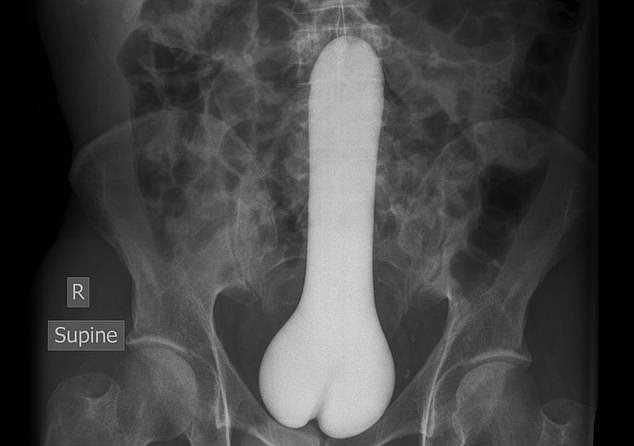

Every year, Americans end up with different types of objects stuck in their rectums.

It was found that the rectum is the most common place for bizarre items to get stuck. Some of the objects include household items such as aerosol can, plastic pill bottle, beer bottle, and a plastic cigar holder.

- ‘Has vibrator in rectum and tried to remove it with screwdriver and lacerated rectum; object in colon now.’